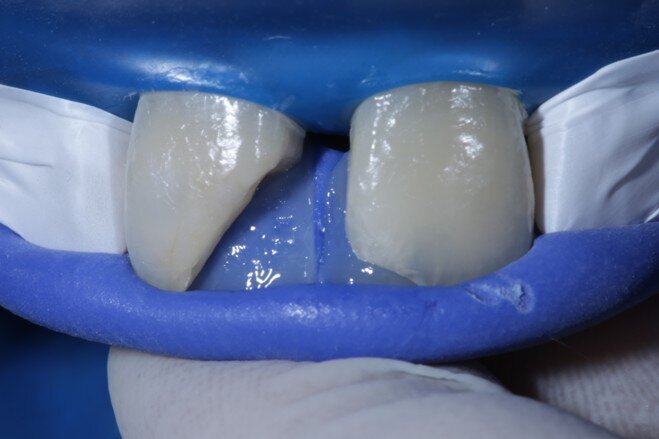

Two weeks later, the shade [ Fig 3 ] stabilized and the teeth were ready for bonding. We observed that the central incisors were still darker than the neighboring teeth. Direct composite veneers were planned with the help of a lab made wax up [ Fig 4 ] and a putty index. Bevels were placed and most of the preparation was in enamel. After the total etch protocol, 5th generation bonding agent was used. 3M Z350XT shades were used for the build up. A2 Enamel shade was used for the palatal shell [ Fig 6 ] and the proximal walls [ Fig 11 ].

Fig 6 Enamel shade for palatal shell on putty index

Fig 7 Enamel shade merged with the teeth